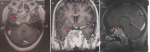

Brain magnetic resonance imaging (MRI) combined with venous MR angiography demonstrated thrombosis of the right lateral sinus extending into the ipsilateral internal jugular vein. Imaging also revealed an invasive intra-sellar mass compressing the optic chiasm, filling the sphenoid sinus, and eroding the sellar floor-highly suggestive of an aggressive pituitary neoplasm (Figure 1, Figure 2, Figure 3).

Figure 1: (A,B,C) magnetic resonance imaging showing an invasive intra-sellar mass compressing the optic chiasm and completely filling the sphenoid sinus (red arrow)